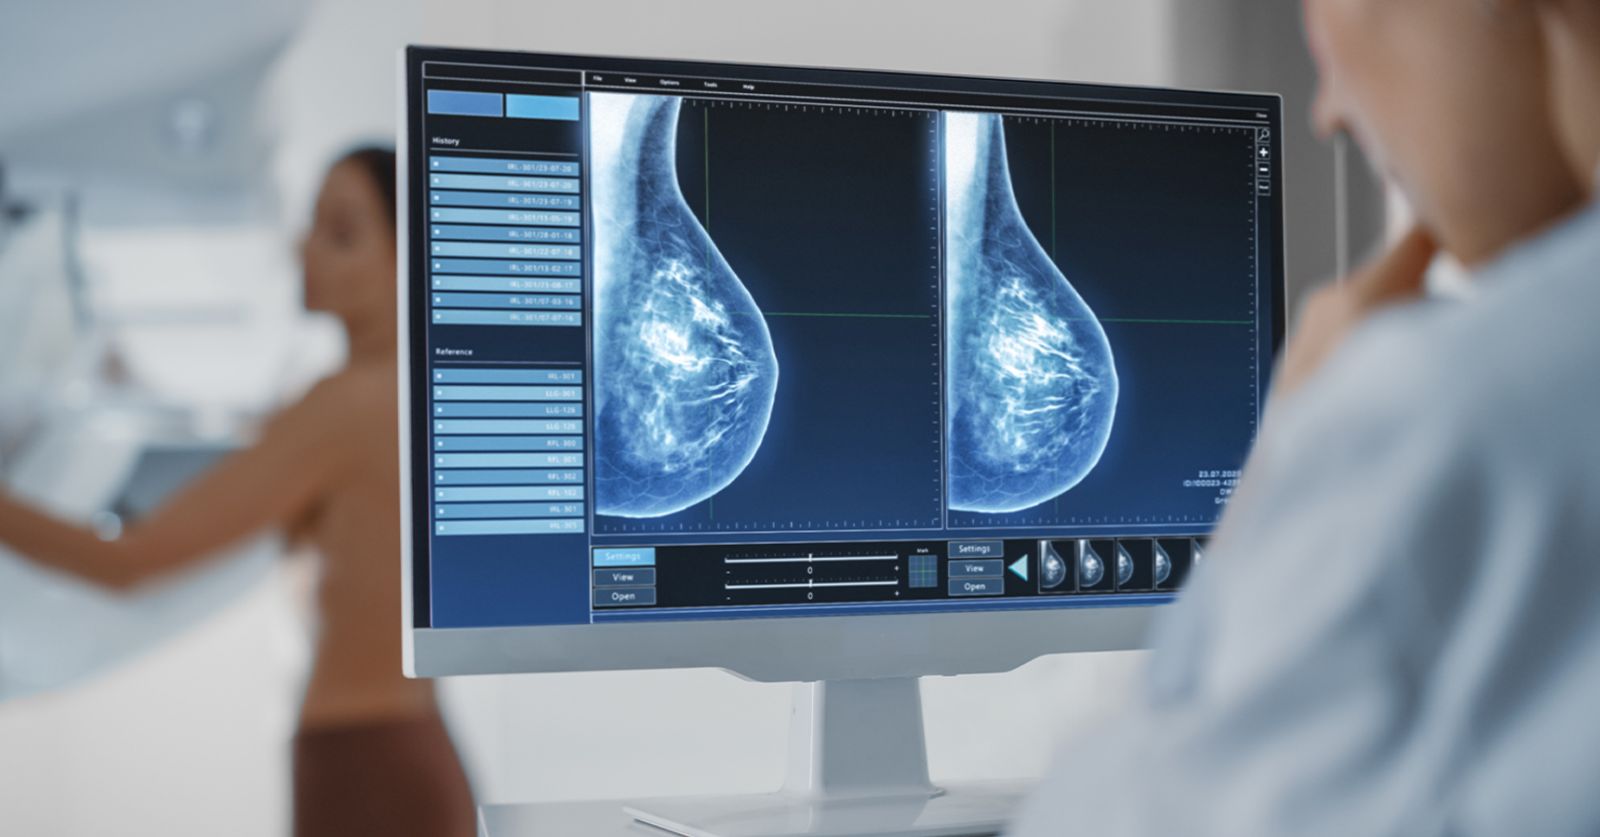

Chụp tuyến vú

Bằng máy chụp X-quang đặc biệt, hình ảnh của tuyến vú hiện trên phim chụp cho phép quan sát các tổn thương ác tính ngay từ khi rất sớm, mới hình thành. Phụ nữ có nguy cơ cao, nên đi chụp tuyến vú từ 40 tuổi, mỗi năm 1 lần. Phụ nữ có nguy cơ thấp hoặc trung bình cũng nên đi chụp từ 50 tuổi trở lên, 1-2 năm/ lần.

Những phụ nữ có đột biến gene BRCA có nguy cơ mắc bệnh ung thư vú và ung thư buồng trứng rất cao, phải được tầm soát ung thư vú ở tuổi trẻ hơn và có thể phải sử dụng MRI (Magnetic Resonance Imaging) để sàng lọc.

Chụp X-quang tuyến vú chẩn đoán xác định ung thư vú.